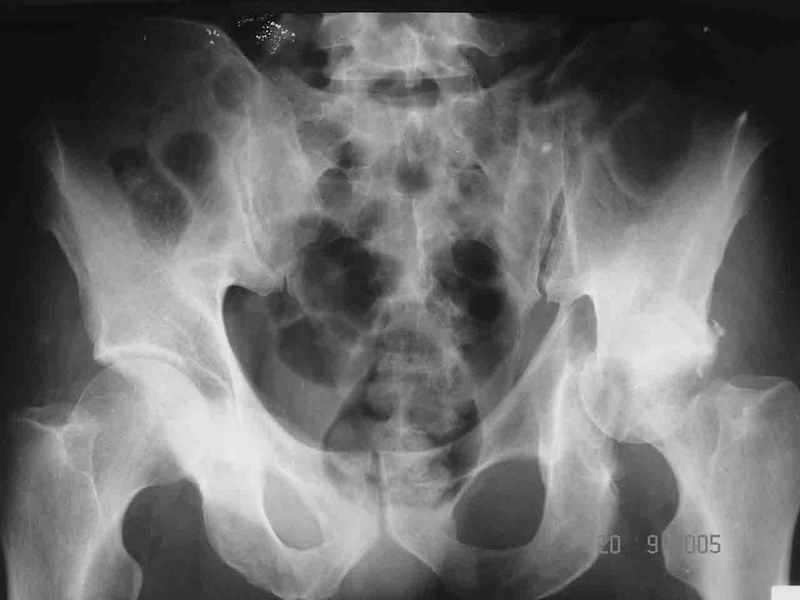

Re: Перелом acetabulum и проксимального отдела бед

Alexey Smirnov 26 Сентябрь 2005, 23:36

Привет! Вот недавно прооперировали похожий на ваш случай - впадина + шейка (правда у нас впадина поперечный+задний край). После травмы прошло 4 недели. мужчине 46 лет. С такой комбинацией все показания к первичному протезированию. Морально и технически мы к этому уже созрели.Но больной не собрал денег на протез. Выполнили остеосинтез впадины и шейки, прекрасно понимая, что головка вскоре рассосется, мы хотя бы надемся что к этому времени таз срастется, как говорится создали все условия для дальнейшего протезирования (может, и протез в последующем подешевле будет, в смысле, без укрепляющего кольца?). Привет Рункову!

Смирнов Алексей.

Рунков 27 Сентябрь 2005, 09:57

Привет Алекей! Сделано неплохо, поздравляю, хотя второй винтик можно было бы и подлиннее в шейку загнать! Пара вопроов: доступ такой же? головка была свободной или висела на капсуле?